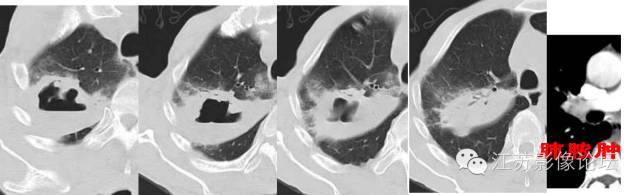

肺部结节的CT鉴别特征

脓腔见于炎性病灶

倍增时间是指肿瘤体积增加1倍的时间,常把球形病灶的直径增加25%所需的时间作为倍增时间。实性恶性结节的倍增时间为40-360天,良性结节为小于1个月或大于16个月。